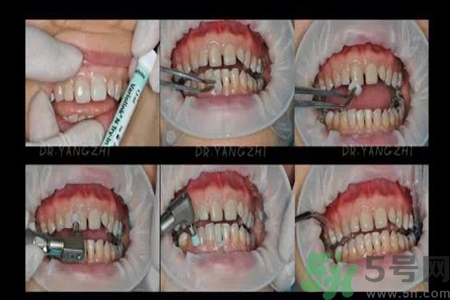

四環(huán)素牙分類

四環(huán)素牙是什么?四環(huán)素牙是怎么形成的?

輕度四環(huán)素牙

白堊色不透明區(qū)至少累及患牙牙面的一半,牙齒無(wú)光澤,牙體肥厚,有時(shí)候還會(huì)看到牙齒表面被磨損掉。

中度四環(huán)素牙

有明顯的磨損,有些四環(huán)素牙已經(jīng)是棕色。

重度四環(huán)素牙

牙齒被破壞。牙齒廣泛著色,妻顏色科接近黑色,牙齒看上去有侵蝕的外觀。